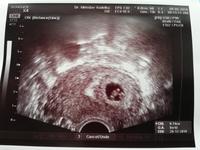

Včera první navsteva dr. Podle ms 6+5tt podle utz 6+4tt 😊 srdíčko bije, neudržela jsem slzy😍, termín porodu 29.12. 😊 6.6 poradna a dostanu průkazku 🙂